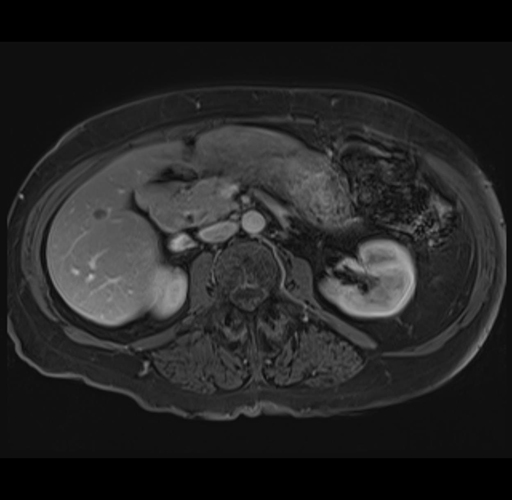

MRI T1